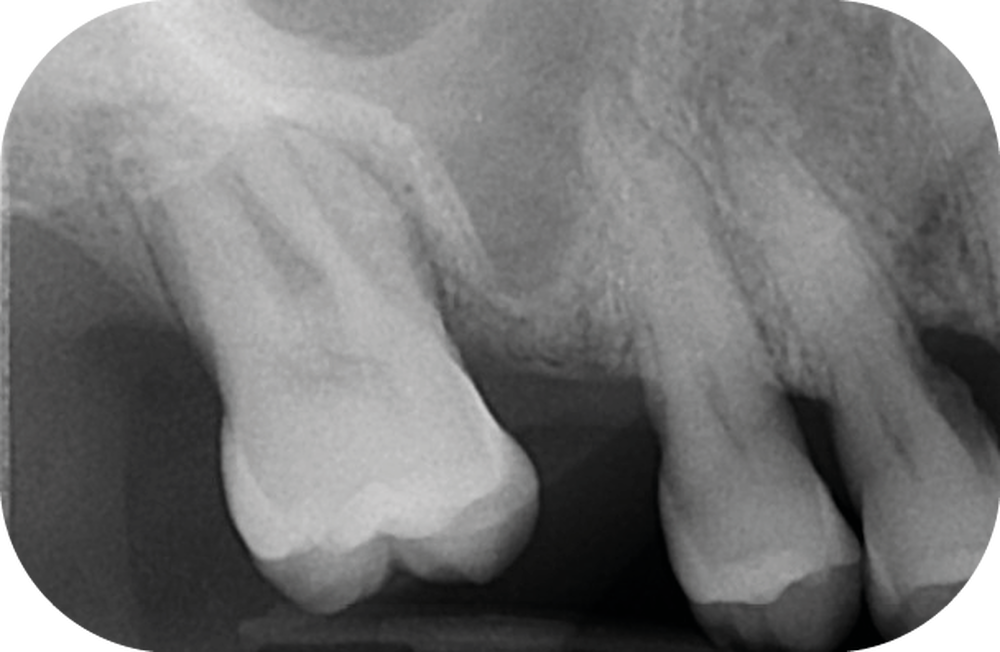

La perte d’une ou plusieurs dents entraîne la perte des points de contact, responsables de la stabilité et de la continuité de l’arcade. Par conséquent, une avulsion a pour première conséquence la migration ou la version d’une ou plusieurs dents distales (fig. 1 et 2). Cela est vrai en antérieur comme en postérieur.

L’âge de survenue de l’extraction semble avoir une importance sur l’apparition des migrations et des versions : si l’édentement intervient après 26 ans, les conséquences sont moins fréquentes [9].